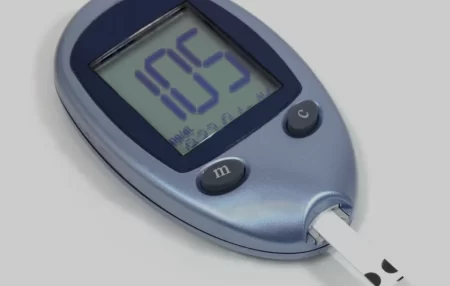

Type 2 Diabetes ICD-10: Understanding the Classification System

Precision and accuracy are crucial when it comes to the coding and classification of medical information. This is especially true…

In the ever-evolving landscape of healthcare, it is crucial to understand medical codes that aid in accurate diagnosis and billing.…